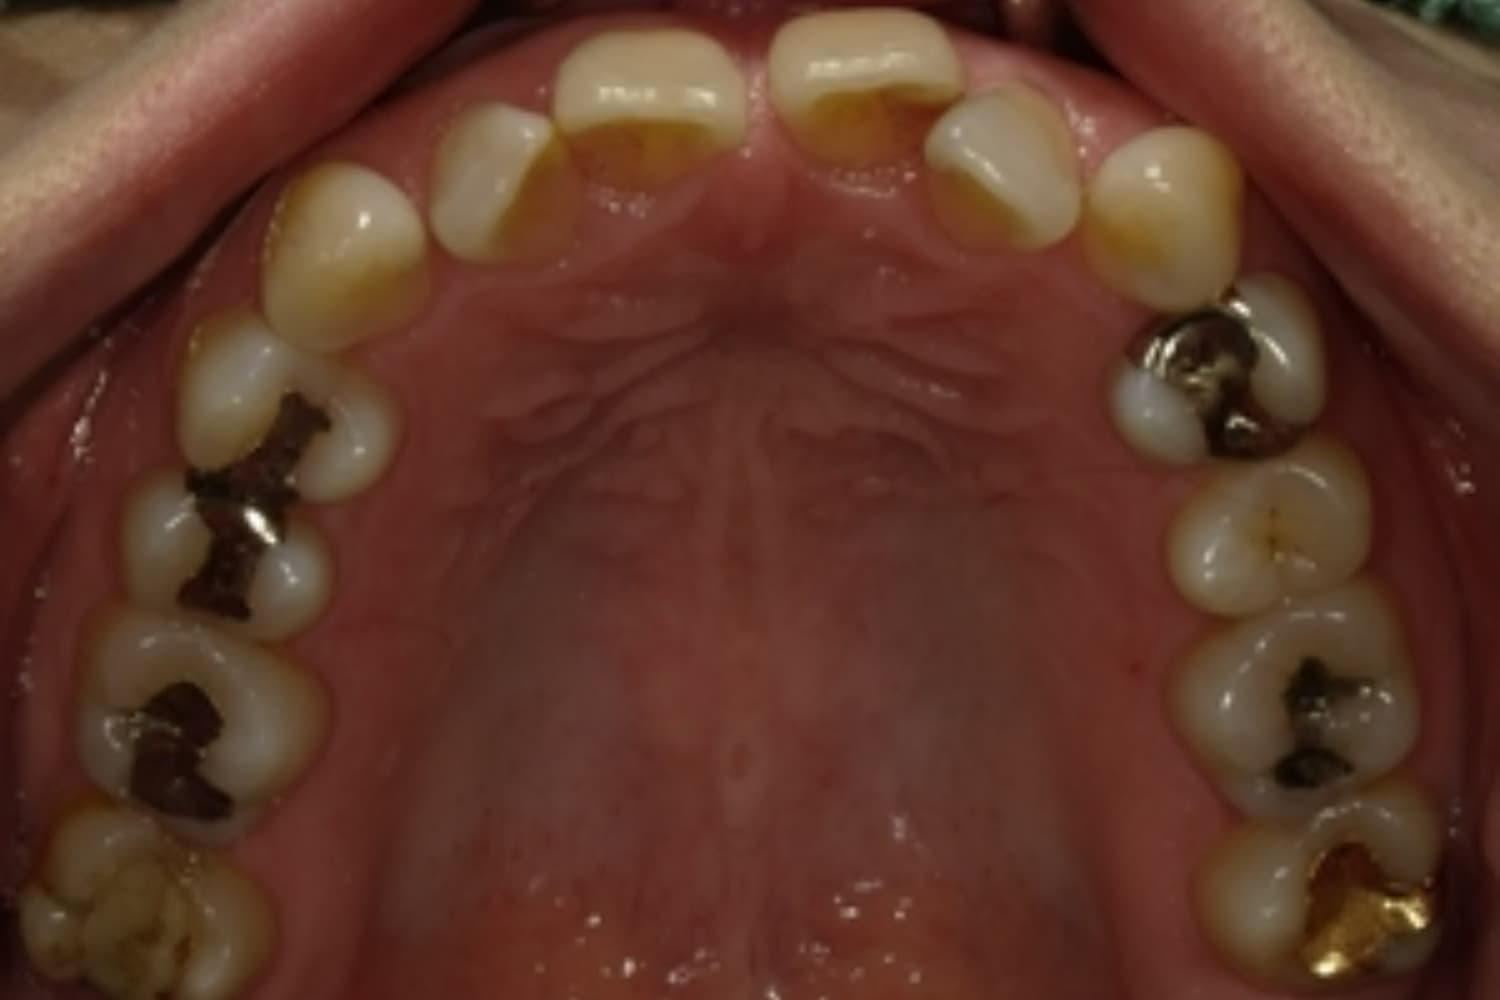

すきっぱ(空隙歯列)2

Before

After

気になる前歯の隙間と前歯のガタガタをマウスピース矯正(インビザライン)にて治療

治療期間

1年

費用

88万円(税込)